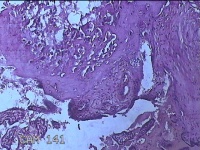

胎盘组织

性别

女

年龄

35岁

临床诊断

胎膜早破 早产

一般病史

停经36+1周,阴道流液3天。

标本名称

大体所见

灰白暗红色胎盘组织18x15.5x2.3㎝一个,表面光滑,血管清晰,颜色发暗,绒毛面结节状,轻度糜烂,表面有少许凝血块,切面见绒毛内有部分淤血,边缘蜕膜可见多个小血肿,脐带15x1.5x0.8㎝,切断脐带,见脐血管内有凝血块。